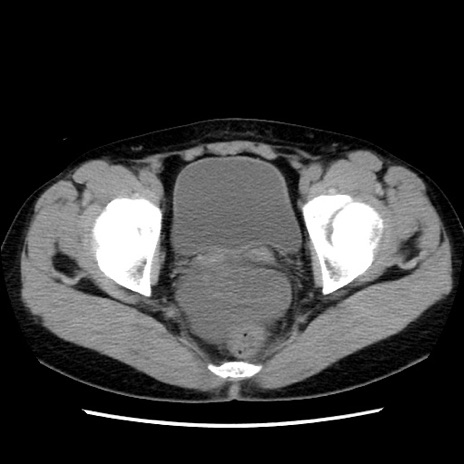

症例10(横断像)

【症例】 50歳代女性

【主訴】 腹痛

【現病歴】前日生レバーを食べた。今朝に排便あり。 昼前に突然発症の腹痛を生じ、当院救急外来を受診した。

【既往歴】 子宮筋腫にてで子宮全摘後

【身体所見】 意識清明、腹部:平坦、軟、下腹部やや左を中心に圧痛・反跳痛あり、筋性防御あり

【データ】WBC 7800、CRP 0.07